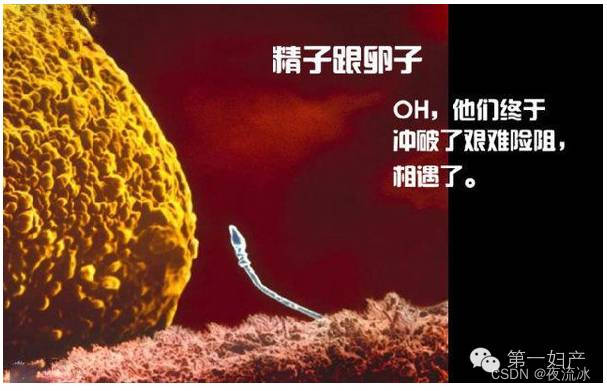

受孕:一个小蝌蚪游向输卵管黏液膜褶内的一个卵子

两个精子钻入一个卵子的壳内

一个精子的纵切面。遗传物质在精子的头部。